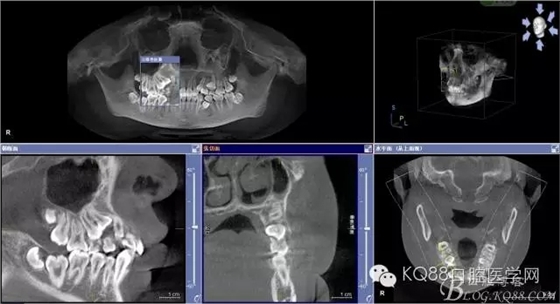

圖2.術前cbct檢查:54、55乳牙滯留,14、15埋伏阻生,14位于15的上方。

圖3.全景片檢查:14位于15與13之間,正畸科要求拔除14,難度可想而知。54、55滯留。

圖4.從局部影像,可以看出14牙冠位于15牙冠與13牙根之間。

圖5.水平剖面觀:14牙冠緊鄰15與13牙根之間,要求分牙一定要小心謹慎